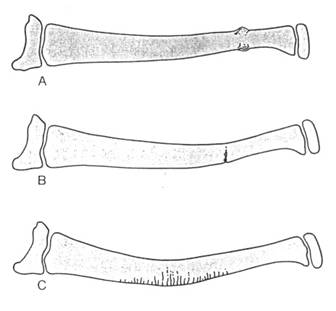

小児の骨格系の特異性に基づき単純X線写真から骨折の画像診断の要点について見逃さないコツを含めて、小児不全骨折と骨端線損傷を中心に画像読影する。

小児不全骨折 A:torus fracture B:greenstick fracture C:plastic bowing

torus fx greenstick fx

greenstick fx plastic

bowing

plastic

bowing